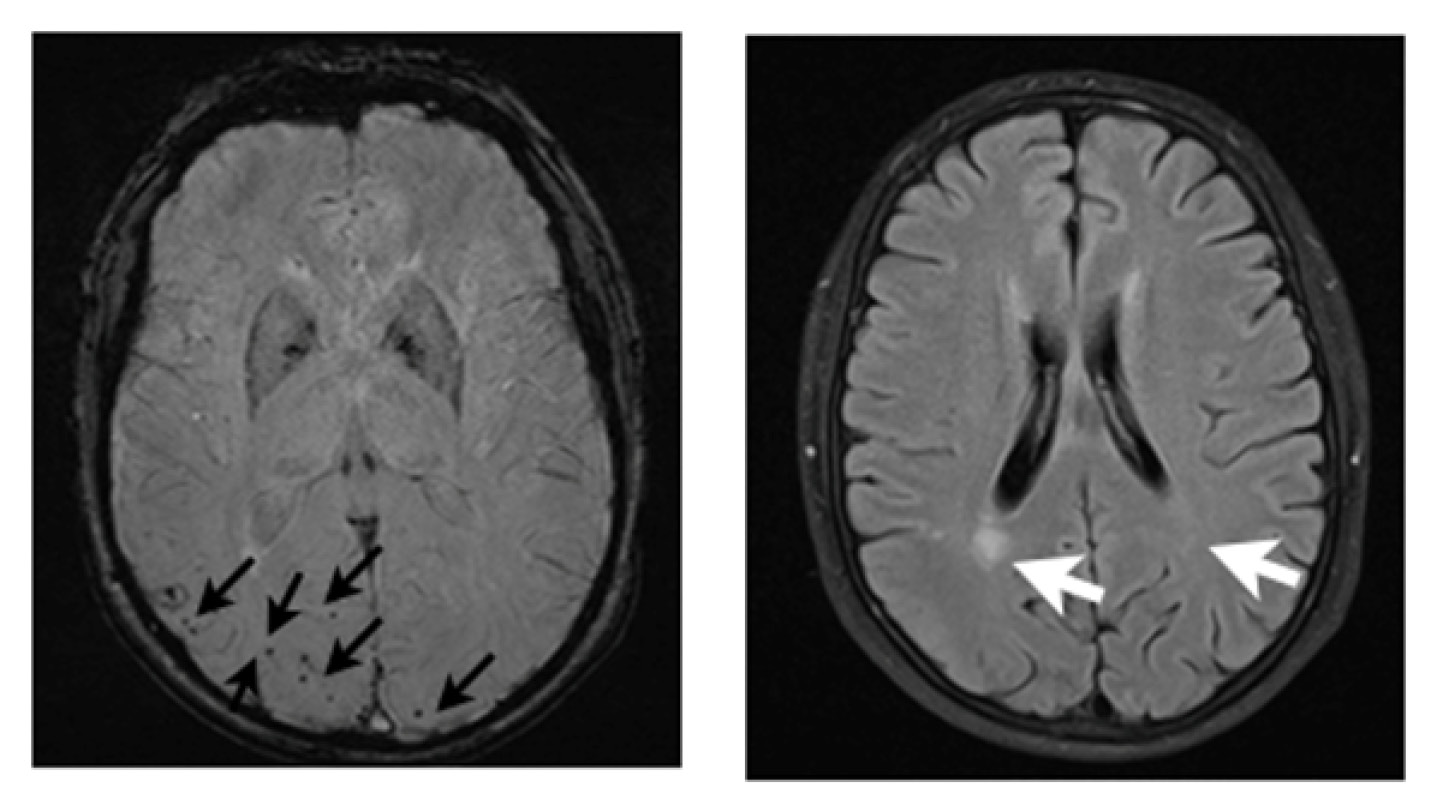

Рис. 1. Результаты магнитно-резонансной томографии головного мозга пациентки при первом обращении в клинику. Представлены результаты исследования в режимах SWI (А, Б) и FLAIR (В). Стрелками указаны очаги множественных микрокровоизлияний и асимметричные зоны лейкоарайоза

Проведённое нейровизуализационное исследование (МРТ головного мозга, рис. 1) выявило множественные микрокровоизлияния, преимущественно расположенные в правой теменной доле. Также отмечен асимметричный лейкоарайоз — выраженные изменения в правой теменной доле, в значительно меньшей степени в левой теменной доле.